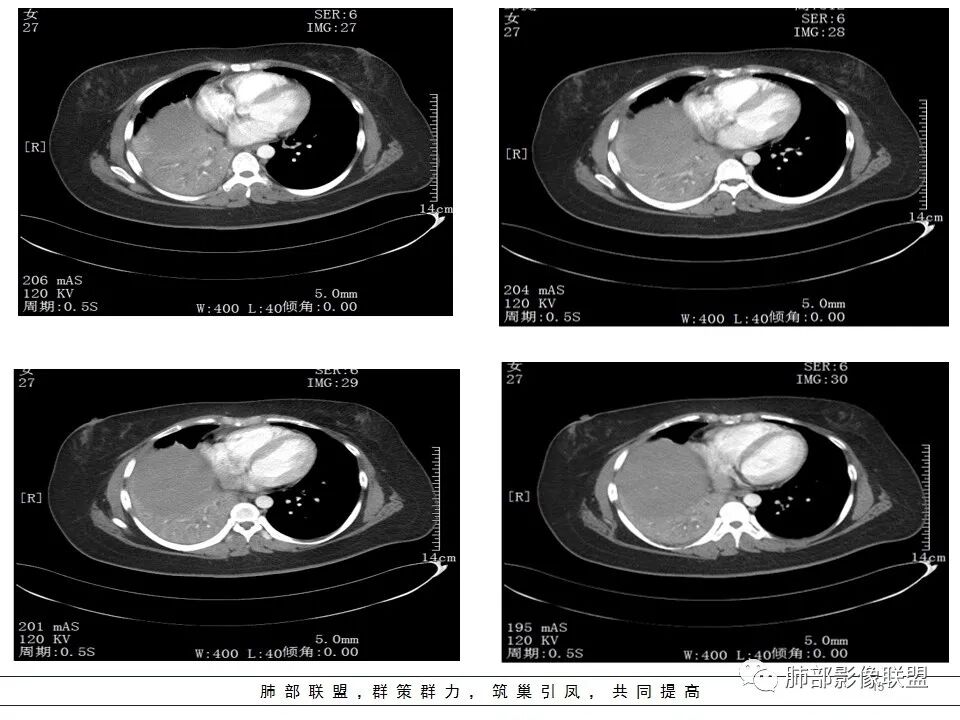

右肺体积缩小,右肺门可见片状影,叶支气管堵塞,呈低密度,无强化,其内似可见点状高密度钙化,病变外周膨隆,右肺下叶大片状致密影,增强后明显强化,其内血管走形自然,右肺下叶呈肺不张改变。纵隔肺门无肿大淋巴结。年轻女性,高热、黄痰来诊。综合考虑:右肺中、下叶综合征合并下叶肺不张,考虑炎性病变,炎性叶支气管阻塞可能性大,早期肺脓肿?结核有点不符合,无胸水,病灶形态太单一。

女,27岁,右肺下叶支气管闭塞,圆形软组织肿块和不张肺,增强不均匀强化,见片状坏死,多个纵隔淋巴结肿大,无钙化空洞及卫星灶;考虑恶性占位,肺肉瘤或鳞癌合并肺不张,鉴别诊断:结核,肺脓肿

CT扫描示右肺下叶支气管堵塞,类圆形大肿块伴胸膜下大片肺实变影,增强扫描类圆形肿块延迟强化,见少量坏死,余实变区增强可见内部血管走行。纵隔见肿大淋巴结。考虑为恶性病变伴右肺下叶肺不张

水晶石头 :

患者青年女性,发热6 天,咳嗽、咳痰3天。为黄脓痰。胸部CT:右肺体积稍小,右中间支气管肿物堵塞,中叶、下叶大片实变不张,与正常肺组织分界清楚。增强实变影明显强化,右下肺支气管近心端见类圆形强化结节影,血管纤细,部分支气管显影变细,纵隔淋巴结肿大。结合无呼吸困难症状,病程长。综合考虑低度恶性病变并阻塞性肺炎,类癌可能大,鉴别结核、淋巴瘤。

本病例特点是中叶病灶和下叶病灶不一样,支气管腔内的病灶又是怎么样的呢?我们要是有沿支气管重建的冠状位、矢状位会更有利于分析。第一,中叶病灶明显粘液样改变、低密度,且低密度区有占位效应、膨隆,确实要考虑粘液表皮样癌。第二,中叶和下叶支气管显示不出来,但血管显示出来了。中叶病灶血管稀疏、细小,下叶病灶血管粗大、走形正常。朝外肺不张实变,不是单纯的肺不张,肺不张一般体积明显缩小、血管聚拢,该病例肿瘤于其中成分不一样,所以上叶部分病灶考虑为下叶病灶占位效应及膈面向上推压引起,中叶萎缩。综合腔内堵塞、纵隔淋巴结肿大要考虑恶性。

支气管层面位置朝下强化明显,支气管腔内、远端是有差异的,腔内哪些是粘液?哪些是肺组织?是单纯实变?还是合并感染?还是外围都是病变?支气管腔内病变?

该病灶明显实变,需鉴别是内朝外,还是外朝内病变。该病灶内血管走形自然,肺门区血管无明显受压移位,且非起源于胸膜,不张肺组织或者不张肺组织夹杂炎性病变。而非典型肺炎型肺癌及外朝内的其他恶性病变。

内朝外病变是支气管腔内病变?还是支气管周围病变呢?如果支气管周围大恶性肿块灶,那其内血管也不应走形自然,应杂乱无章,所以只能是腔内病变引发支气管周围病变。

2.右肺中下叶大片实性密度影,体积有缩小,密度不均,不均匀强化,前份可疑小范围液性密度区。

3.中间段支气管阻塞,腔内隐约见息肉样结节或突入,结节有较明显强化,这很重要,说明它有生命力,强烈提示新生物,而非分泌物或异物等等。

可惜腔内腔外混沌一片,我们不能分辨管壁及管壁外细节,我们不能判断新生物实际大小,不能判断局部支气管彻底破坏还是结节影跨越腔内外。